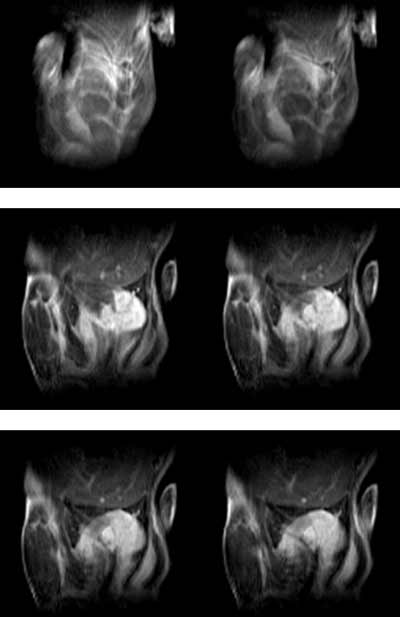

小鼠动物成像实验数据(腹部成像)

小鼠造影剂成像腹部成像数据

小鼠成像腹部成像数据